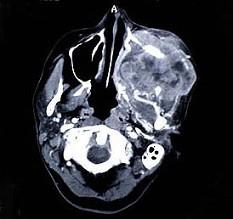

以下关于上颌窦癌(见图)的叙述,哪项是错误的 ( )

A肿瘤发生部位不同可出现不同临床症状 (如鼻塞

B早期无症状而不易发觉

C早期即有明显的骨质破坏

D远处转移较少见

E以鳞状细胞癌为最常见